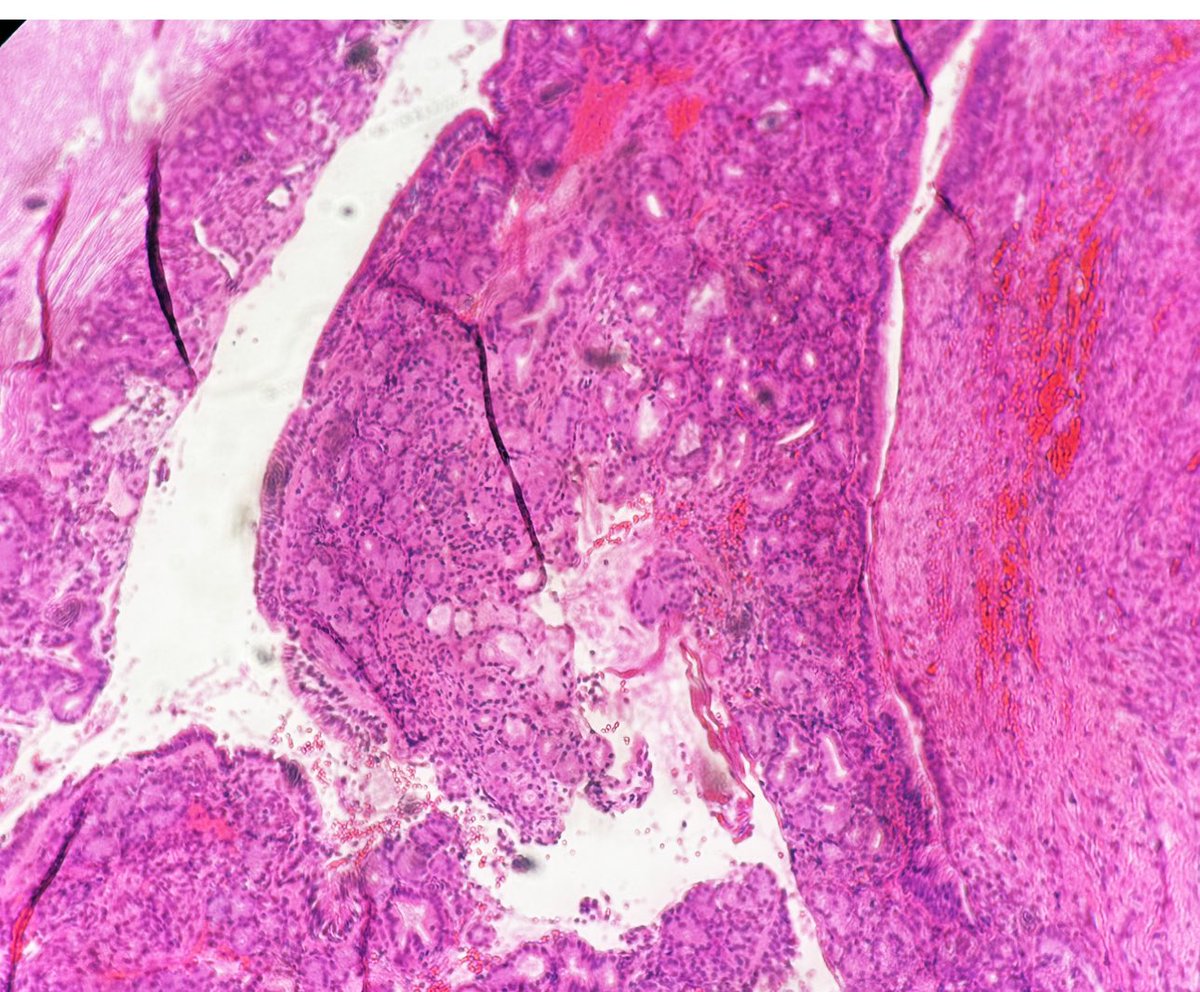

A 70 year old gentleman presented with right sided nasal obstruction and nasal discharge, was found to have a 5 cm right nasal mass. Excision of the mass was performed. What is your opinion? #ENTpath #Headneckpath #Pathtwitter #PathX

A 70 year old gentleman presented with right sided nasal obstruction and nasal discharge, was found to have a 5 cm right nasal mass.

Excision of the mass was performed.

What is your opinion?

#ENTpath

#Headneckpath

#Pathtwitter

#PathX